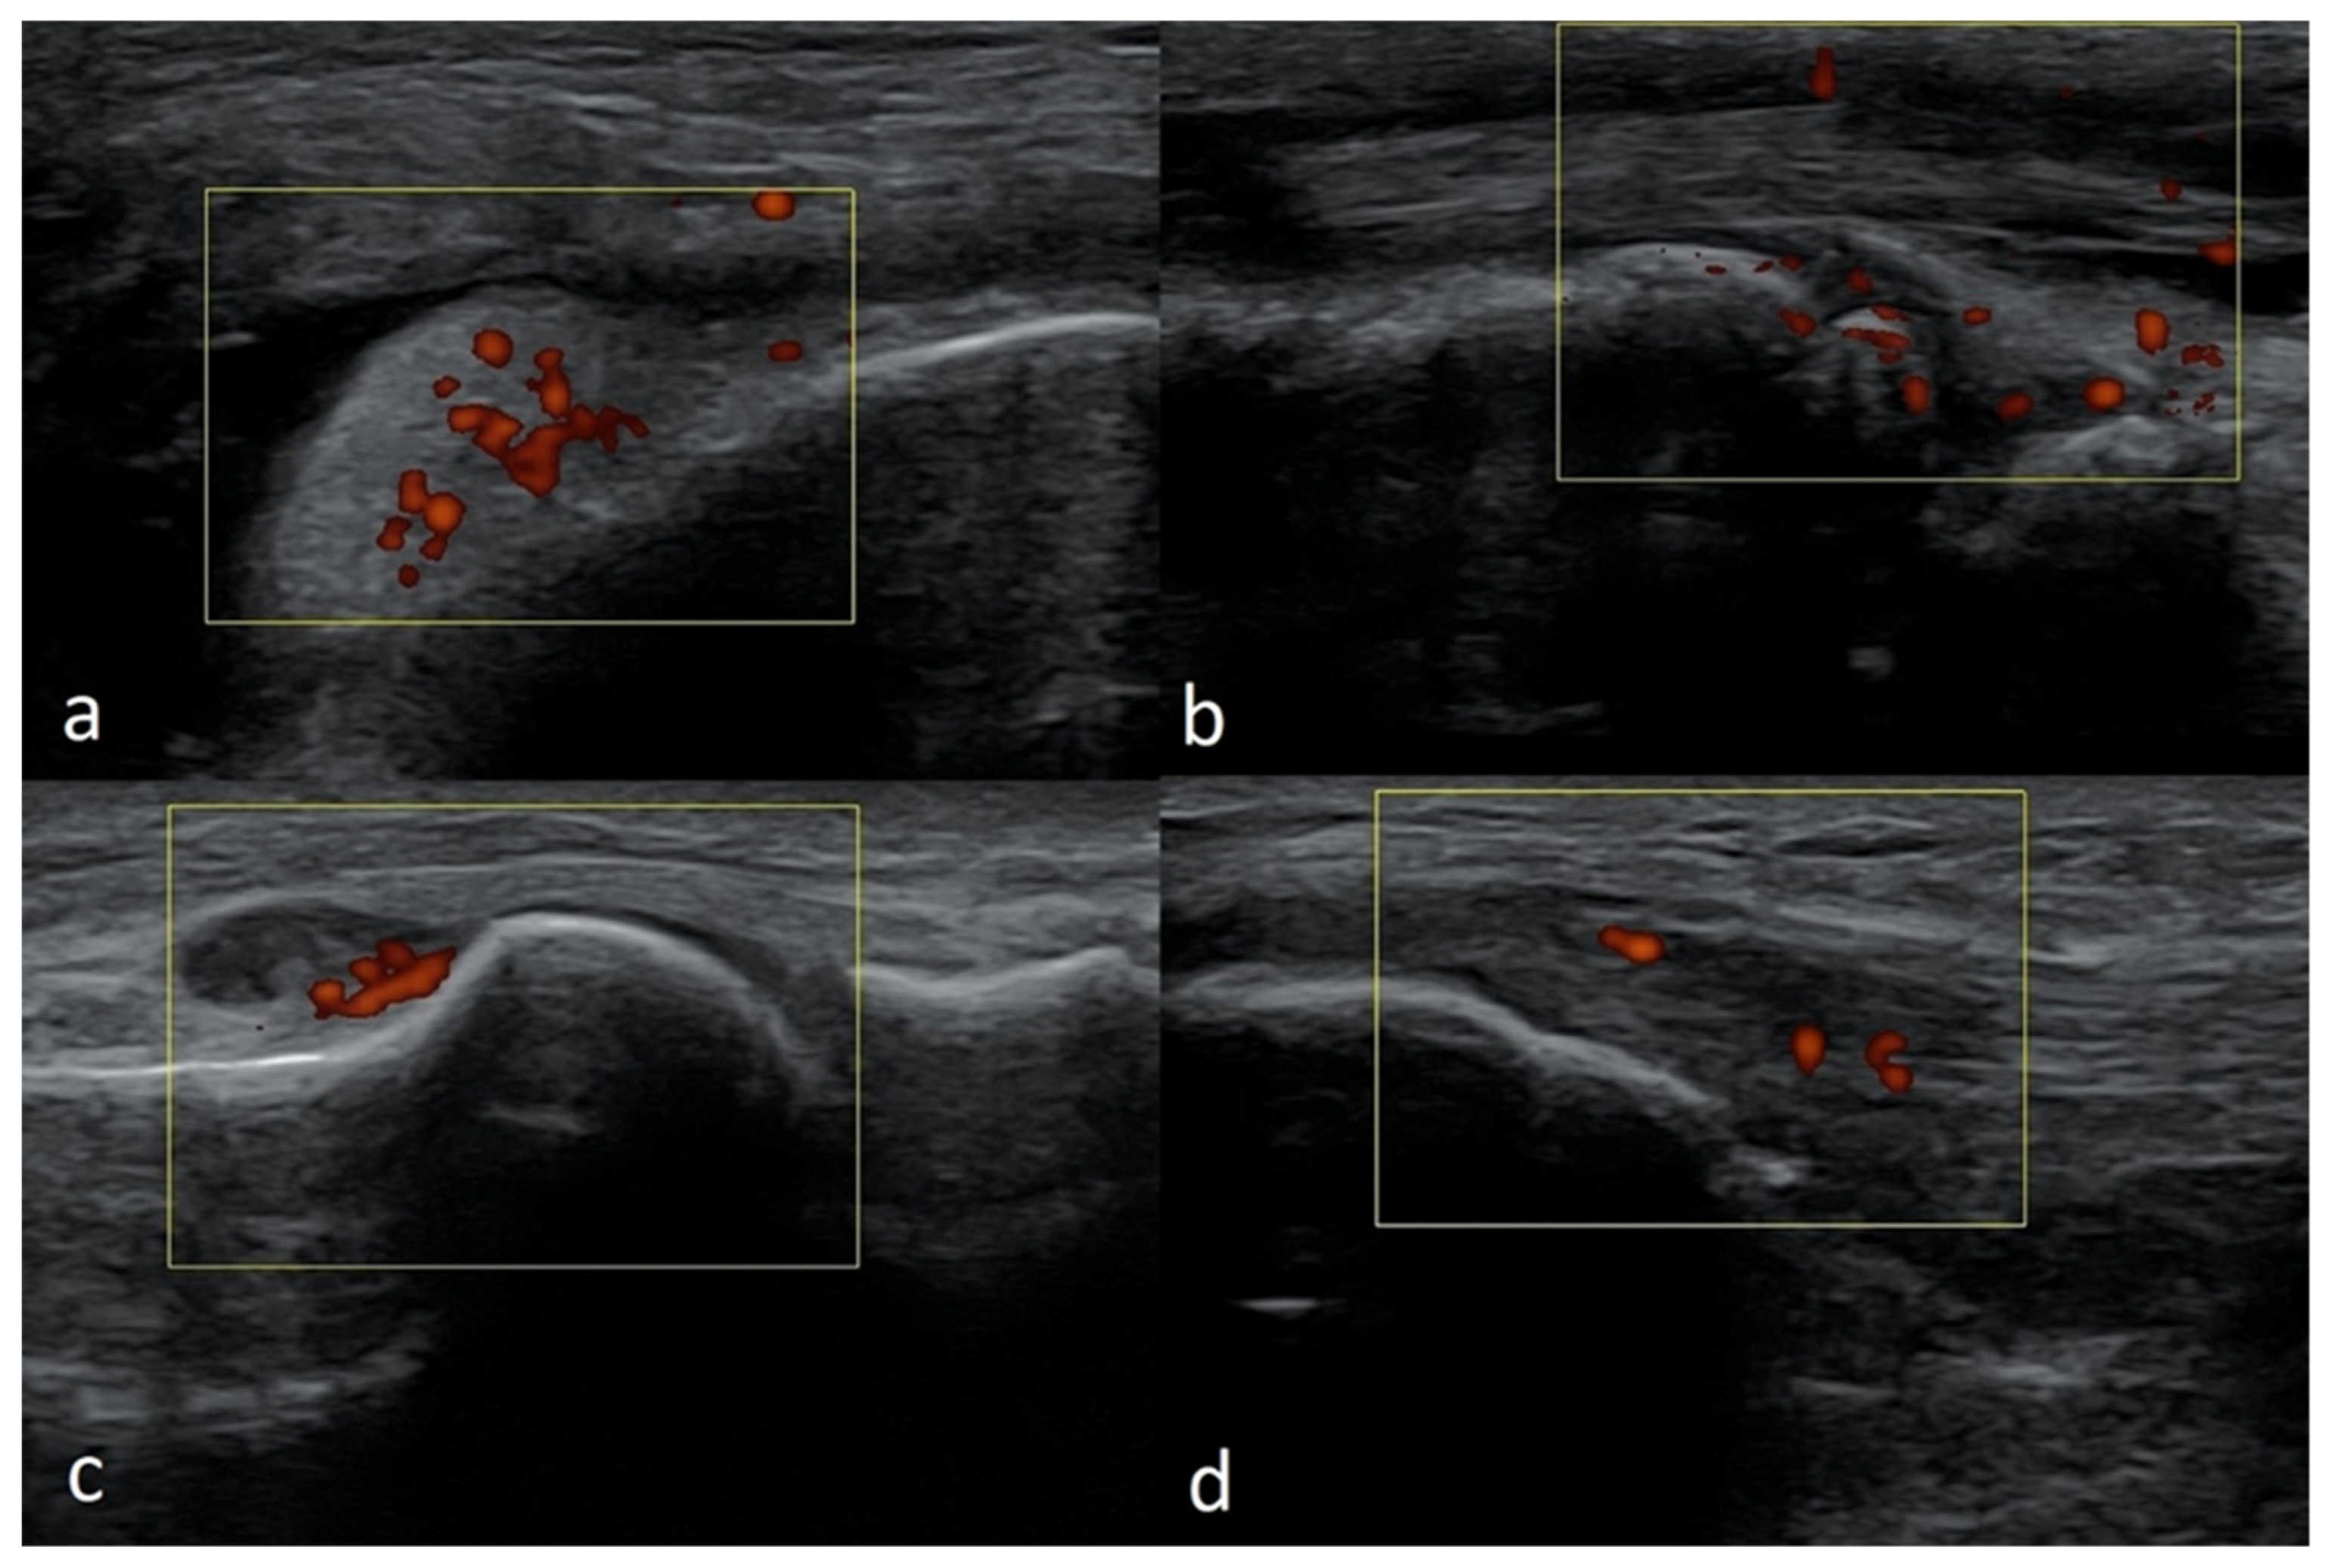

3.2.6. Exudates and Inflammations Affecting Joints

3.2.7. Baker’s Cysts